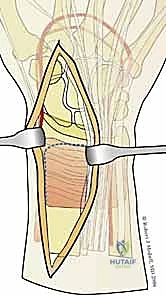

1. المداخل الجراحية (Surgical Approaches)

نظراً لأن الكسر يتم تثبيته من جهات متعددة، قد يستخدم الدكتور هطيف شقوقاً جراحية صغيرة ومدروسة بدلاً من شق واحد كبير.

* المدخل الأمامي (Volar Approach): للوصول إلى الحافة الهلالية والسطح الأمامي لعظم الكعبرة. يتم إبعاد الأوتار والأعصاب (مثل العصب المتوسط) بعناية فائقة.

* المدخل الظهري أو الجانبي (Dorsal/Radial Approaches): شقوق صغيرة إضافية للوصول إلى شظية العمود الكعبري أو الجدار الظهري، مع الحفاظ التام على الأوتار الباسطة.